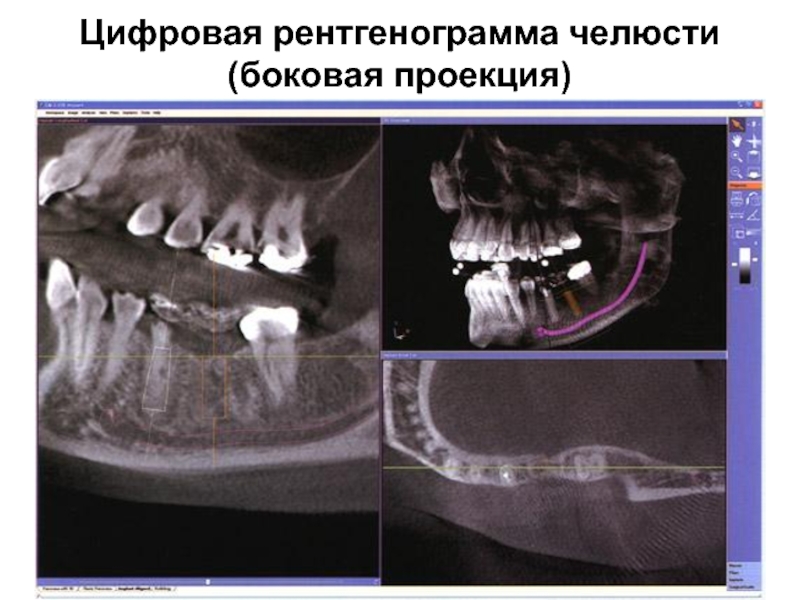

Слайд 9Цифровая рентгенограмма челюсти (боковая проекция)

Цифровая рентгенограмма челюсти  (боковая проекция)